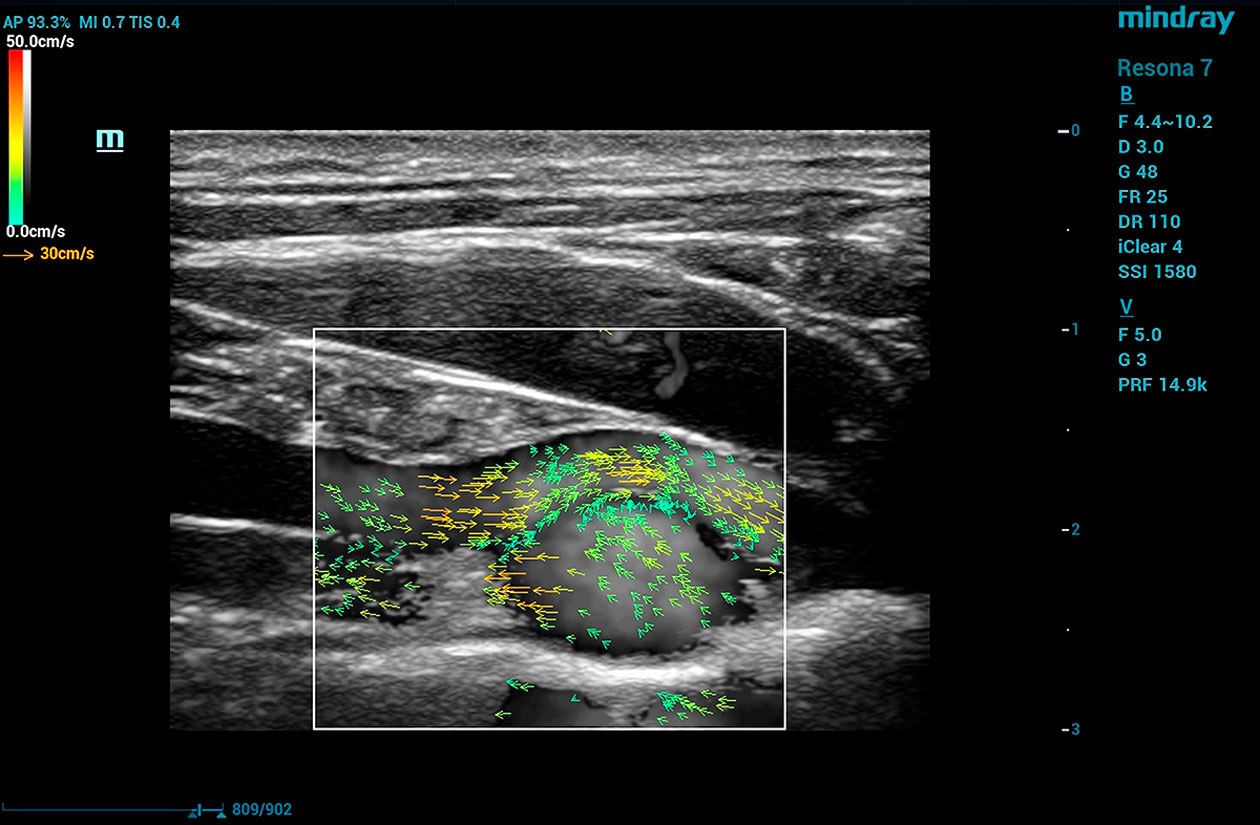

V Flow

V Flow imaging creates a quantitative map of hemodynamic states by tracking the acoustic speckle produced by microstreams of red blood cells as they flow through several non-temporally coherent transmit plane waves. The resulting information is plotted as arrows of varying lengths and colors expressing direction and velocity of blood within the interrogated area.